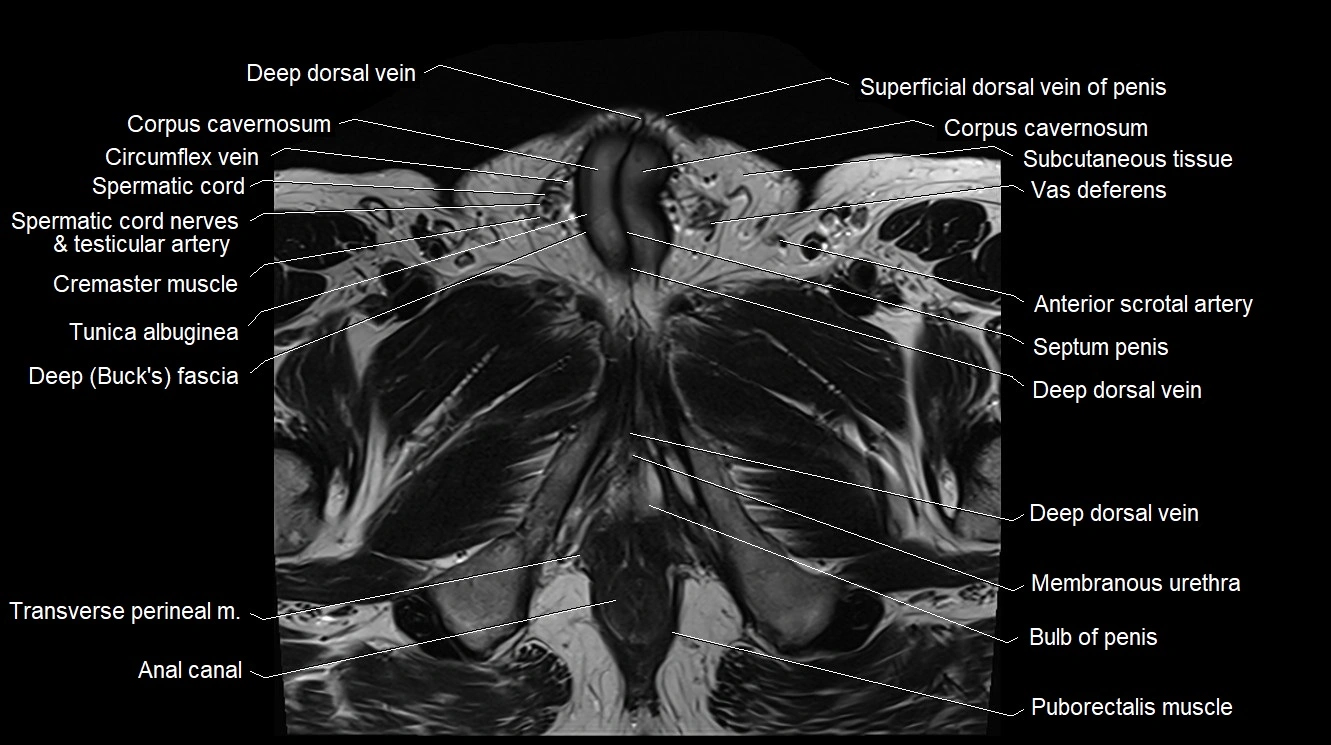

MRI image